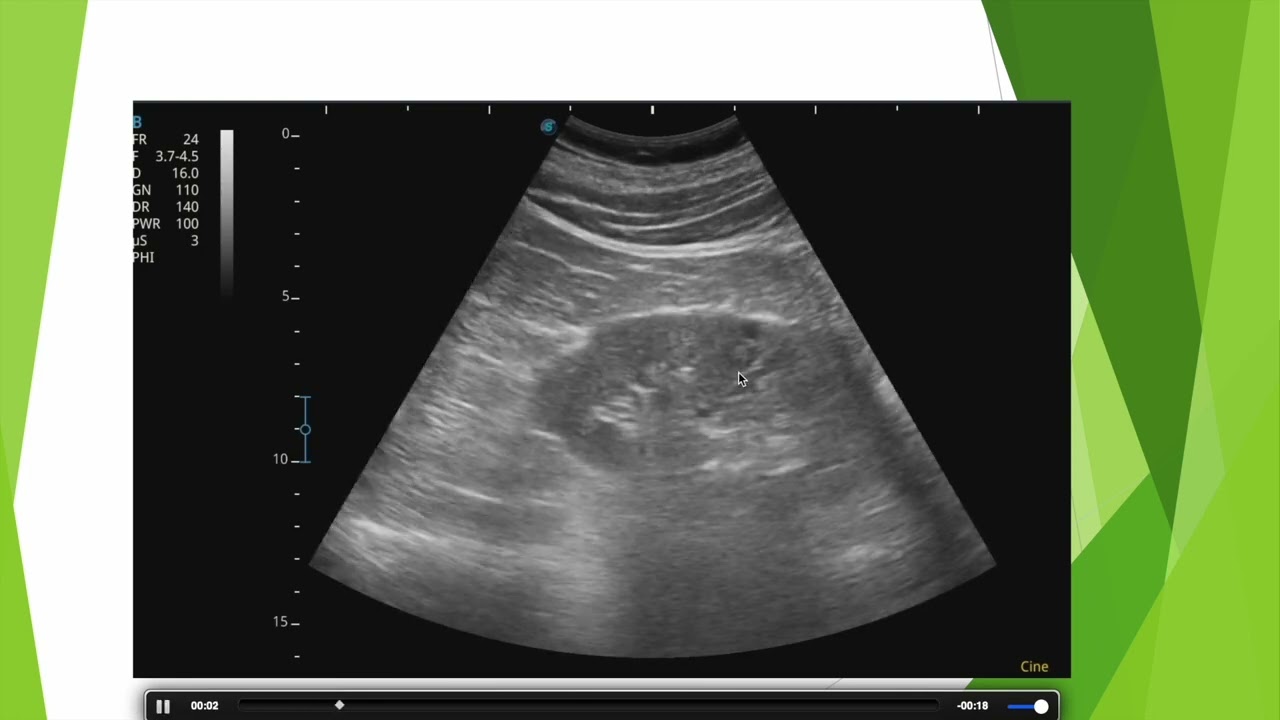

Caractéristiques d'un. cancer mammaire en échographie

Aspect typique d'un adénocarcinome mammaire (cancer mammaire) en échographie. Description de l'aspect de la tumeur principale et d'une métastase ganglionnaire en échographie confirmée en anatomopathologie.